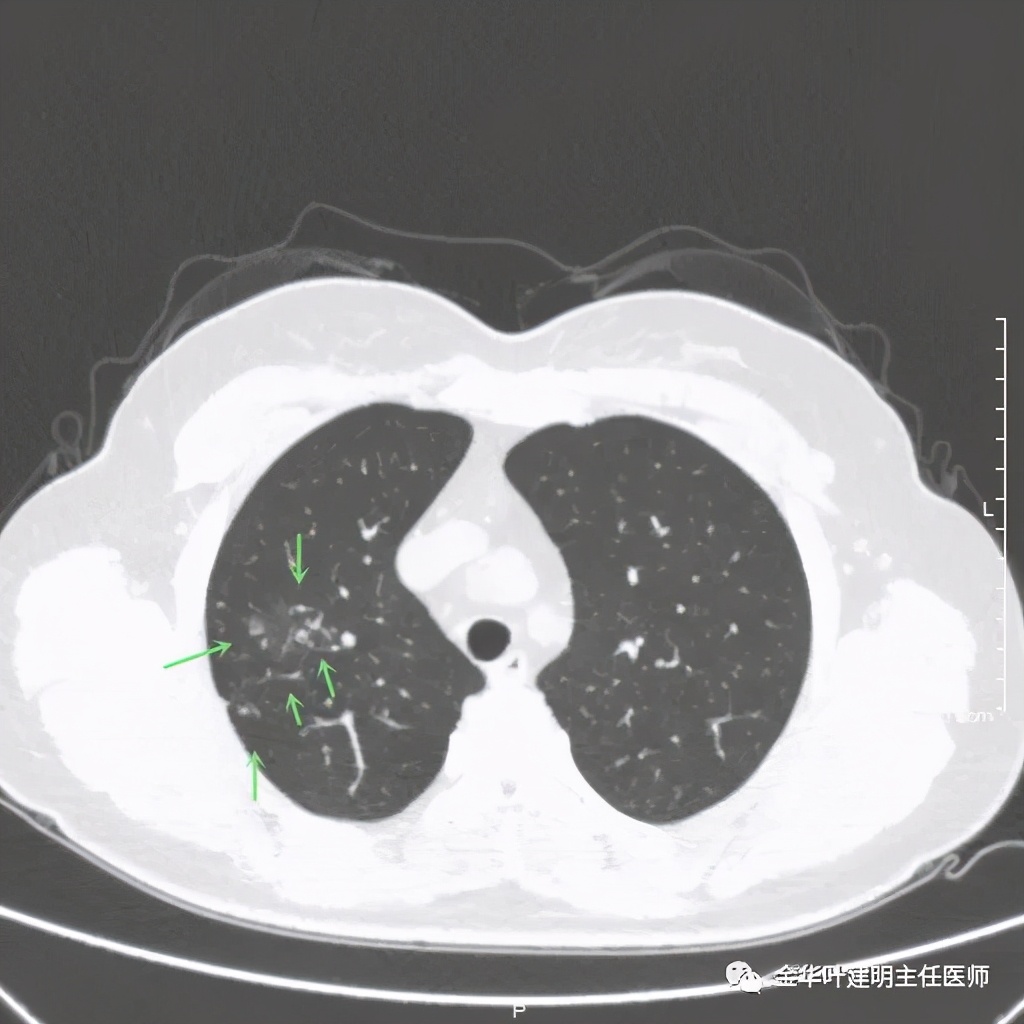

右上叶开始出现病灶,是实性的

病灶比较光滑,密度高,旁边有小的卫星灶,不清爽

绿色箭头示主病灶边有小的实性微小结节,主病灶边缘非常光滑,没有毛刺、分叶等征

主病灶光滑,旁边有不清爽的小斑点状病灶

绿色箭头示病粉旁边有卫星灶,而且密度都高,主病灶也是实性

病灶边散在多发微小实性与似磨玻璃的微小结节

病灶附近不清爽